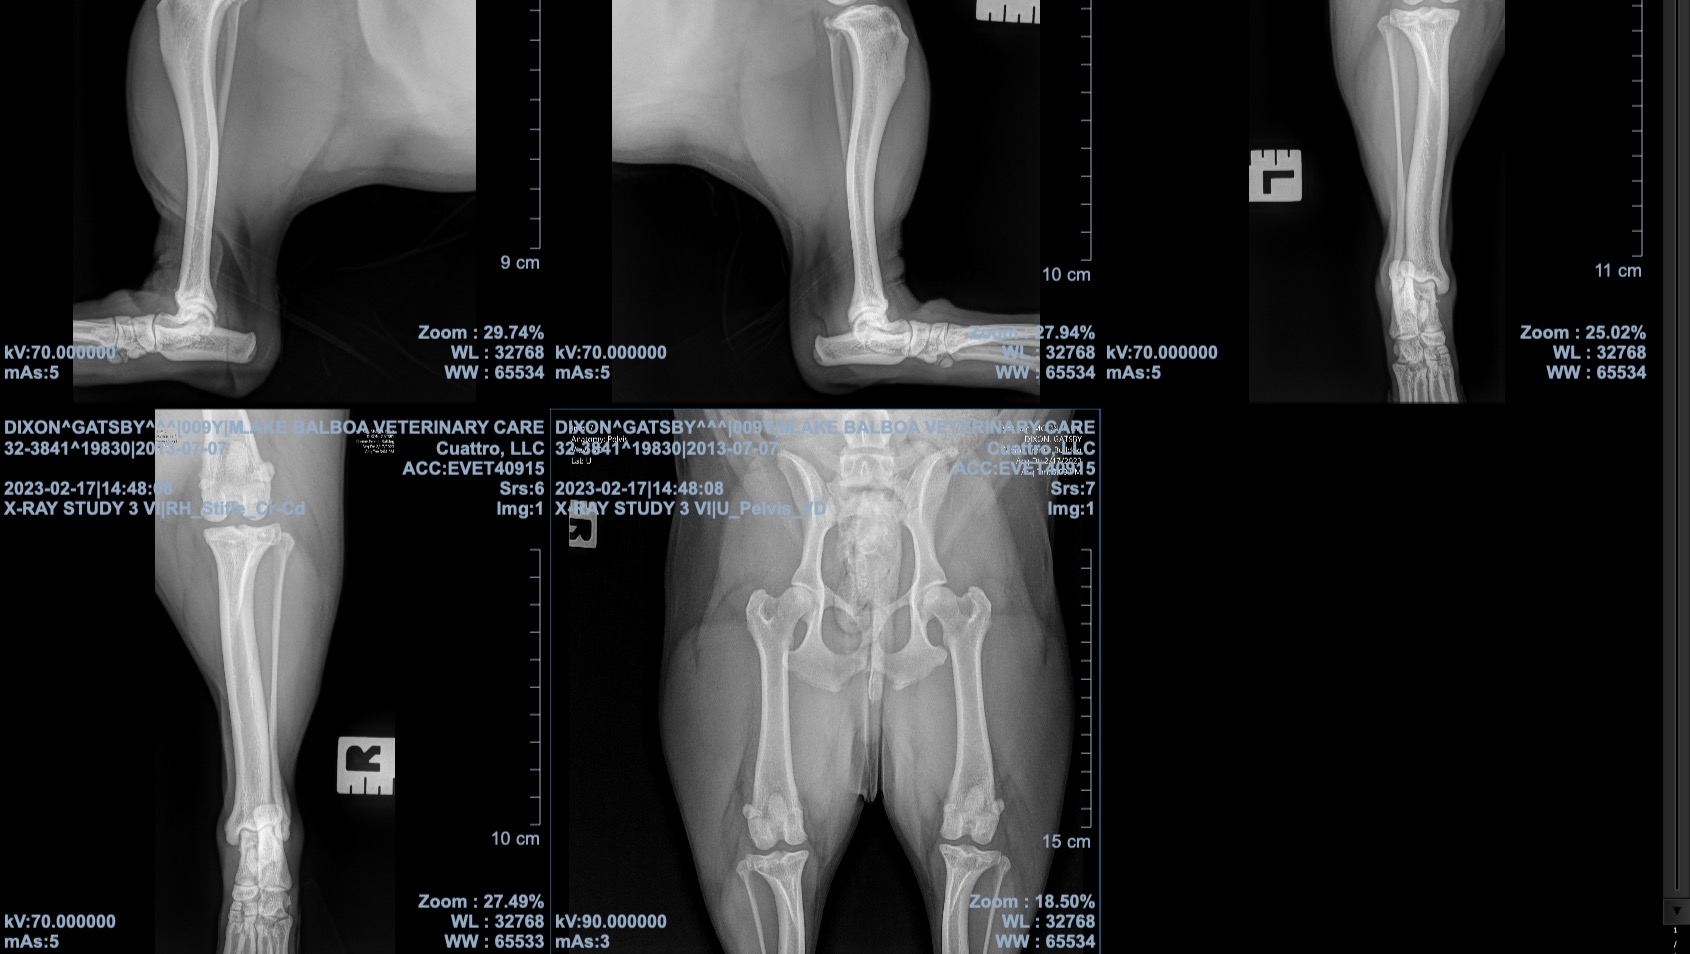

Unfortunately, a couple of weeks ago after a routine day out and years of perfect condition, he got out of his bed in the evening in incredible pain and couldn’t hold himself up. X-rays revealed a torn ACL which is something that could only be fixed with invasive and expensive surgery. Because physical activity is such a huge part of his day-to-day, the effects of limited activity due to injury have been immediate and heartbreaking. He is not just restless and in pain, but sad and low in spirit.

The total cost of surgery is $5,153.46. The initial bill was paid through Scratchpay which is a vet-care financing service that makes funds available to the vet directly (Lake Balboa Veterinary Care in my case) and then has to be paid off bi-weekly. What adds to this challenge is while I use this service regularly, so far I haven't been charged interest. This time, the loan is much higher and must be paid within 6 months to avoid 26.9% interest charges, making this even more nervewracking, and harder to manage. (No interest deadline is Sept. 1, 2023). His post-op X-rays, 8 weeks from now, will be another $365 and are not accounted for in the above surgery cost.